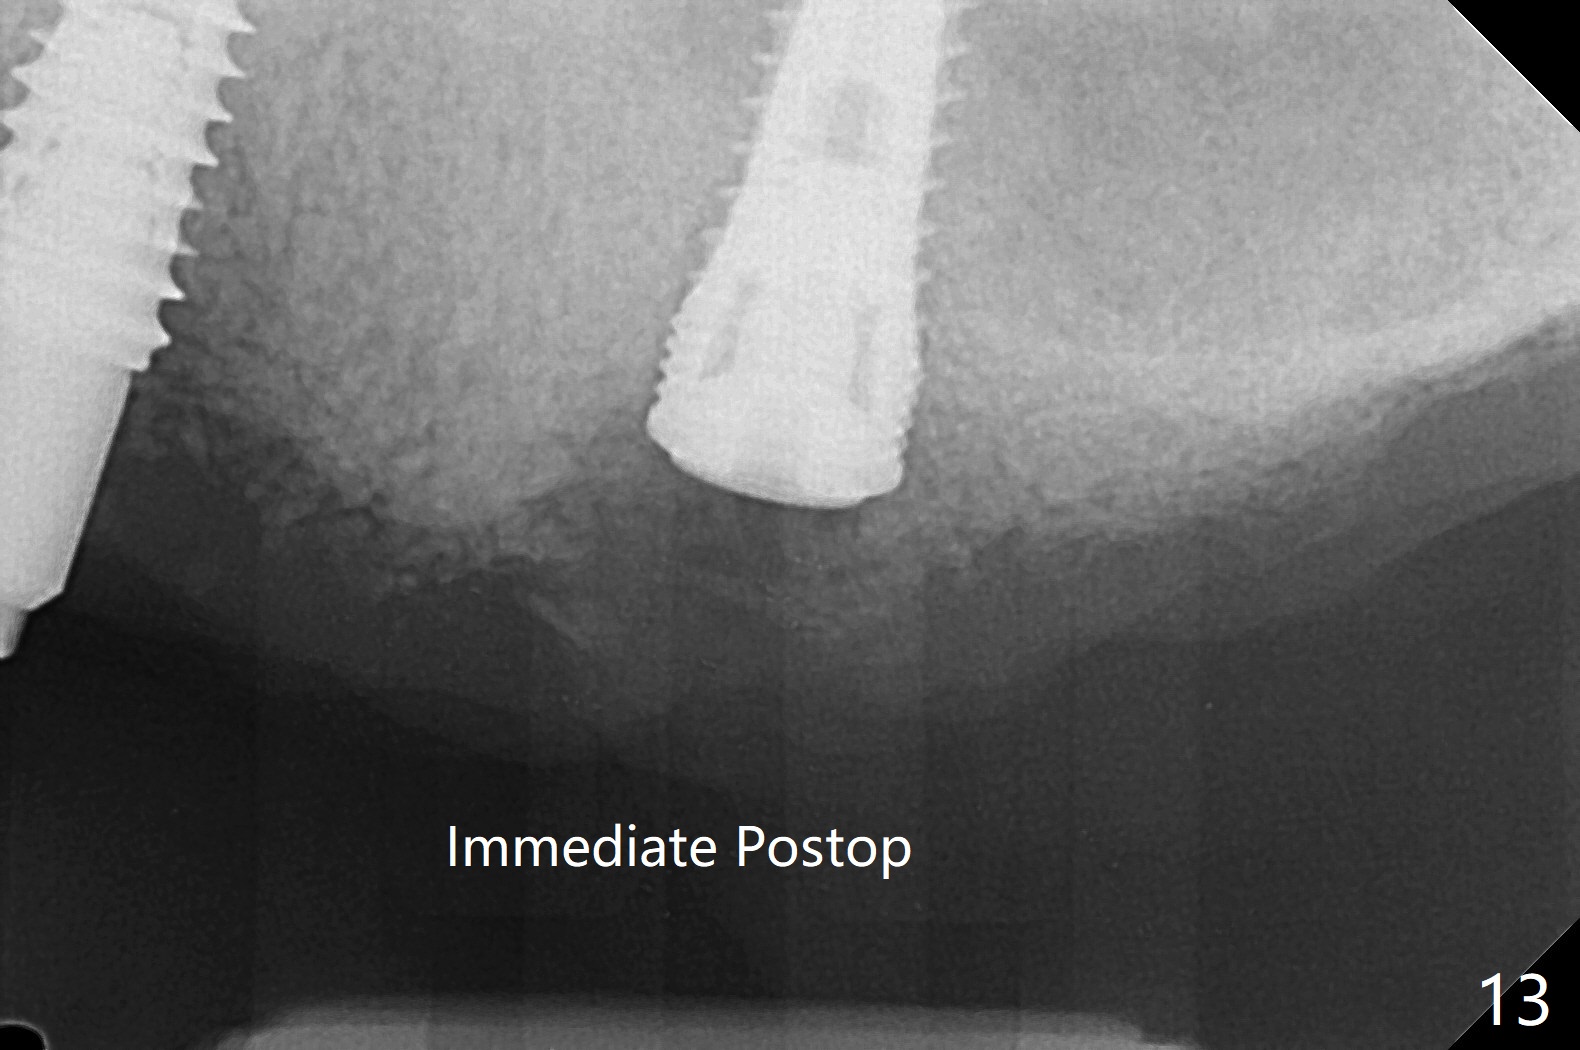

Osteotomy at #13 starts blindly (no incision or tissue punch) with bone expanders. After insertion of parallel pins, intraop CT shows that it is palatal with apparently buccal low bone density (Fig.1); the osteotomy for implant (Fig.2 green) should be shifted buccal and tilted mesial (red, parallel to #11) with incision. In contrast the position, trajectory and depth (Fig.3 <) of the initial osteotomy are acceptable at #11. The implant will be placed as it is (Fig.4). After taking a postop PA (Fig.5), the implant at #11 is placed a little deeper to make sure its slightly subcrestal placement (including distal incision at #11). Following placement of 3.5x4 and 3 mm ball abutments at #11 and 13, cortical allograft with PRF is placed around the implants, especially buccal (Fig.6,7 <). After suturing, the profile of the ball abutments is too low for RPD retention. Due to gravity other than bone density, the number of ball abutments for the maxilla should be more than for the mandible. Soft reline is done to the patient's satisfaction. The retention of the upper RPD after soft reline is satisfactory without pain 7 days postop (Fig.8). The implant at #13 is loose nearly 3 months postop (Fig.9 *: bone loss). The implant is removed while the ball abutment is untightened; the sinus floor is present. It appears that a longer and larger implant is necessary; a 4.5x10 mm dummy implant is unable to be seated deep or achieve primary stability (Fig.10). After sinus lift with 3 mm Bicon osteotome without bone graft, the dummy implant accomplishes the 2 tasks mentioned above (Fig.11). However there is no corresponding definitive implant in stock. Implant system needs to be changed; with a change in implant driver, the depth control is lost. The final implant is placed deep (Fig.12). With back up, stability is lessened; a healing screw is placed; with collagen plug, the wound is sutured (Fig.13). The wound heals 1 week postop (Fig.15). The RPD is soft relined. Retention from the ball abutment at #11 is apparently critical. The RPD and #11 implants (4 months postop) are stable, while the wound at #13 heals 1.5 months postop (Fig.15). There is space around the implant 5.5 months postop (Fig.16 *). The 5x10mm SM implant is found to be loose upon uncover and removed. After debridement, 5.3x8 mm SM and 5.5x9 mm IBS dummy implants are inserted without stability, while 6x9 mm definitive one with stability (Fig.17). Cortical allograft is placed in deficiency areas (*). The osteotomy has no roof (sinus floor), but the sinus membrane is intact. Small amount of bone graft (Fig.18 *) is placed before implantation. There appears to be bone around the new implant (Fig.19 (3D sagittal section) *).